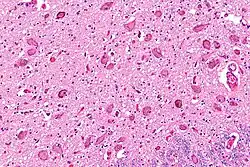

The locus coeruleus (LC) is located in the posterior area of the rostral pons in the lateral floor of the fourth ventricle. It is composed of mostly medium-size neurons. Melanin granules inside the neurons contribute to its blue colour. Thus, it is also known as the blue nucleus, or the nucleus pigmentosus pontis (heavily pigmented pontine nucleus).[5] The neuromelanin is formed by the polymerization of norepinephrine and is analogous to the black dopamine-based neuromelanin in the substantia nigra.

The locus coeruleus is affected in many forms of neurodegenerative diseases: genetic and idiopathic Parkinson's disease, progressive supranuclear palsy, Pick's disease, and Alzheimer's disease. It is also affected in Down syndrome.[29] For example, there is up to 80% loss of locus coeruleus neurons in Alzheimer's disease,[30] Mouse models of Alzheimer's disease show accelerated progression after chemical destruction of the locus coeruleus.[31] Neurofibrillary tangles, a primary biomarker of Alzheimer's disease, may be found in the locus coeruleus decades before any clinical symptoms.[32] The norepinephrine from locus coeruleus cells in addition to its neurotransmitter role locally diffuses from "varicosities". As such it provides an endogenous anti-inflammatory agent in the microenvironment around the neurons, glial cells, and blood vessels in the neocortex and hippocampus.[18] It has been shown that norepinephrine stimulates mouse microglia to suppress Aβ-induced production of cytokines and promotes phagocytosis of Aβ.[18] This suggests that degeneration of the locus coeruleus might be responsible for increased Aβ deposition in AD brains.[18] Degeneration of pigmented neurons in this region in Alzheimer's and Parkinson's disease can be visualized in vivo with Neuromelanin MRI.[33] Since the marked degeneration of locus coeruleus, and the neuroprotective properties of noradrenaline, Ian Robertson proposed the "Noradrenergic Theory of Cognitive Reserve" [34] which postulates that the upregulation of the locus coeruleus-noradrenergic system throughout the lifespan may enhance cognitive stimulation contributing to cognitive reserve preventing from neurodegeneration. Evidence appear to support this theory reporting the locus coeruleus integrity primarily responsible of biological brain maintenance,[35][36][37] including brain clearance,[38] cognitive efficiency, and reduced neuropathological burden.[35][39][40][41]